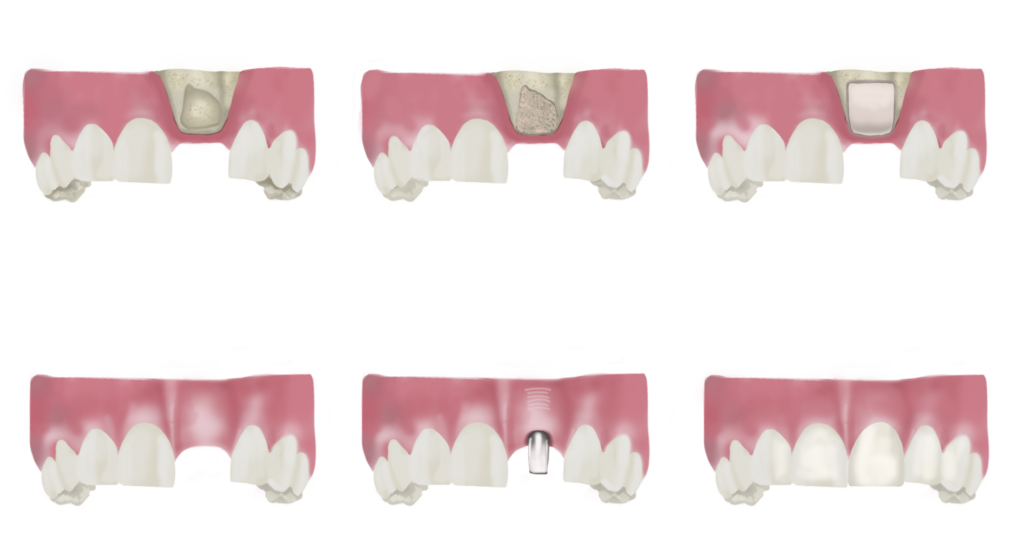

- Rehabilitació de l’equilibri oclusal mitjançant pròtesis o implants que ens permetin col·locar de nou les dents que s’hagin perdut i reequilibrar la mossegada i la funció. Sempre utilitzant materials no tòxics.

Els implants son el gran malentès de la nostra societat: en general els consultant els temen però senzillament és por a allò desconegut, un cop fets tots diuen que no ha estat res! A La Clínica Verda som conscients que si posem implants de titani aquest ha de ser l’únic metall de la boca per a no crear galvanisme… Per això, sempre recomanem eliminar altres metalls presents abans de passar a la fase de col·locació dels implants. D’aquesta manera ajudem al cos a tolerar molt millor els tractaments i a mantenir l’equilibri i el benestar.

Un cop tenim l’os suficient, ja podem col·locar implants i pròtesis sobre implants per rehabilitar la mossegada i l’òptima funció de la boca.

PRÒTESIS

A La Clínica Verda no utilitzem metalls en les pròtesis que col·loquem. Prioritzem materials nobles i molt resistents com el Zirconi, el Disilicat de liti o la porcellana. Materials que confereixen una gran estètica però també una gran resistència sense cap mena de toxicitat per l’organisme.

Sempre que fem una rehabilitació protètica reequilibrem la boca segons els principis d’equilibri i funció òptims preconitzats per la rehabilitació neuro-oclusal, basada en un estudi minuciós de les conseqüències posturals i osteopàtiques de l’encaix de les dents i dels moviments a l’hora de mastegar. D’aquesta manera ajudem al consultant a mantenir o retrobar i millorar el seu equilibri.